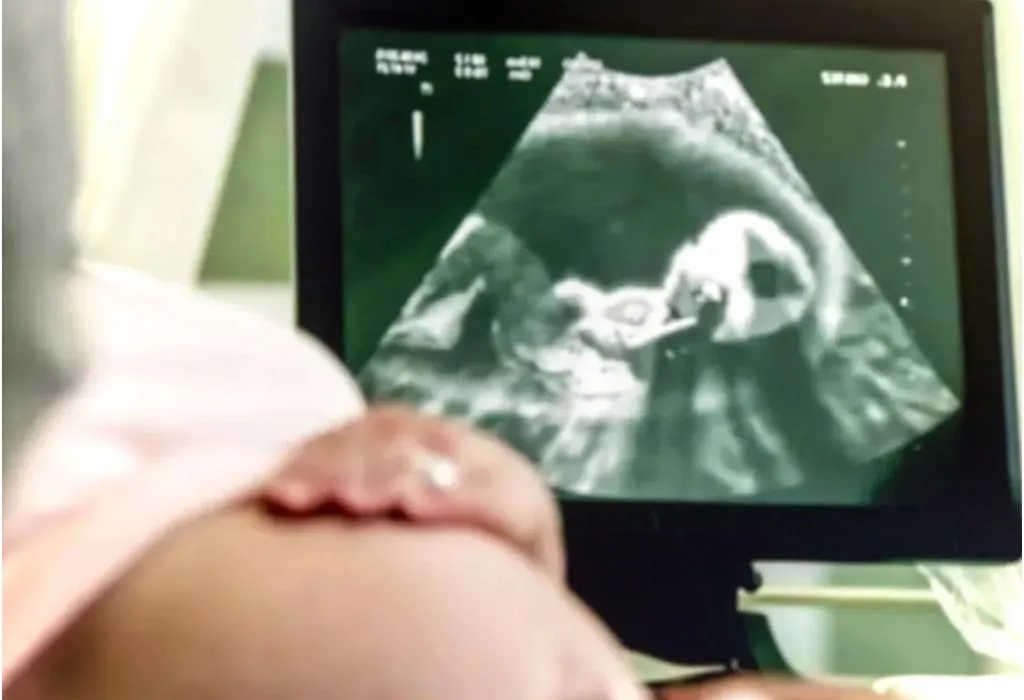

- Any deformities or abnormalities in your unborn baby’s kidneys can be detected during your routine prenatal ultrasound. Around the 20th week of pregnancy, your doctor might be able to determine if there is any kidney-related problem in your baby.

- Foetal multicystic dysplastic can be detected during an ultrasound exam (7).